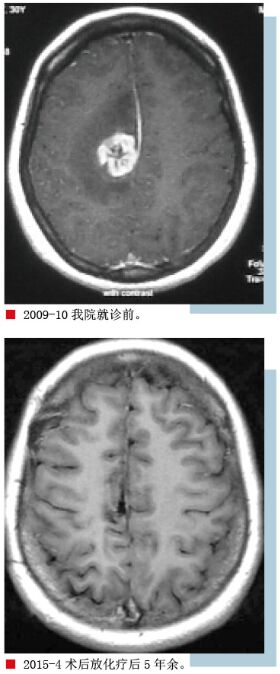

患者冯某某,女,30岁,因“发现颅内占位近1年”于2009年10月19日第一次入我院。2008年因发作性头晕到当地医院就诊,经检查发现右顶叶病变,未予处理,头晕症状自行缓解。2009年1月复查头颅MR示病变无明显变化,未予治疗。2009年3月患者夜晚再次出现发作性头晕,继而意识不清,口吐白沫,双眼上翻,维持10分钟后症状缓解,半小时后意识恢复,对发作情形不能回忆,未予重视。当年5月再发作一次,症状同前,6月在当地医院行伽马刀治疗,10月再次出现头晕症状而前来我院进一步治疗。查体:生命体征正常,颅神经检查无异常,四肢肌力、肌张力正常,无病理征。入院后复查MR示病变范围增大,病变周围水肿明显,遂于11月23日在全麻下行“右顶叶深部病变切除术”,病理回报:(右顶叶)星形细胞瘤,WHOⅡ级。

2009年12月~2010年3月行4周期化疗,2周期化疗后复查头颅MR示:术区周边强化灶范围较前缩小,术区周围水肿已基本消失。2010年4月~2010年5月行头部适形放疗,治疗后患者未再诉头晕。治疗结束给予出院,定期复查。

2015年4月患者复查头颅MR示未出现复发征象,现治疗后5年余,已达临床治愈。